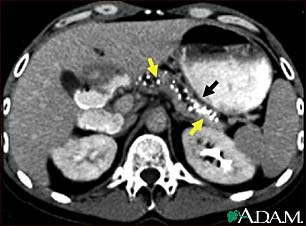

Pancreatitis, chronic - CT scan

CT scan of the upper abdomen showing multiple white-colored calcifications. These occur in chronic pancreatitis.